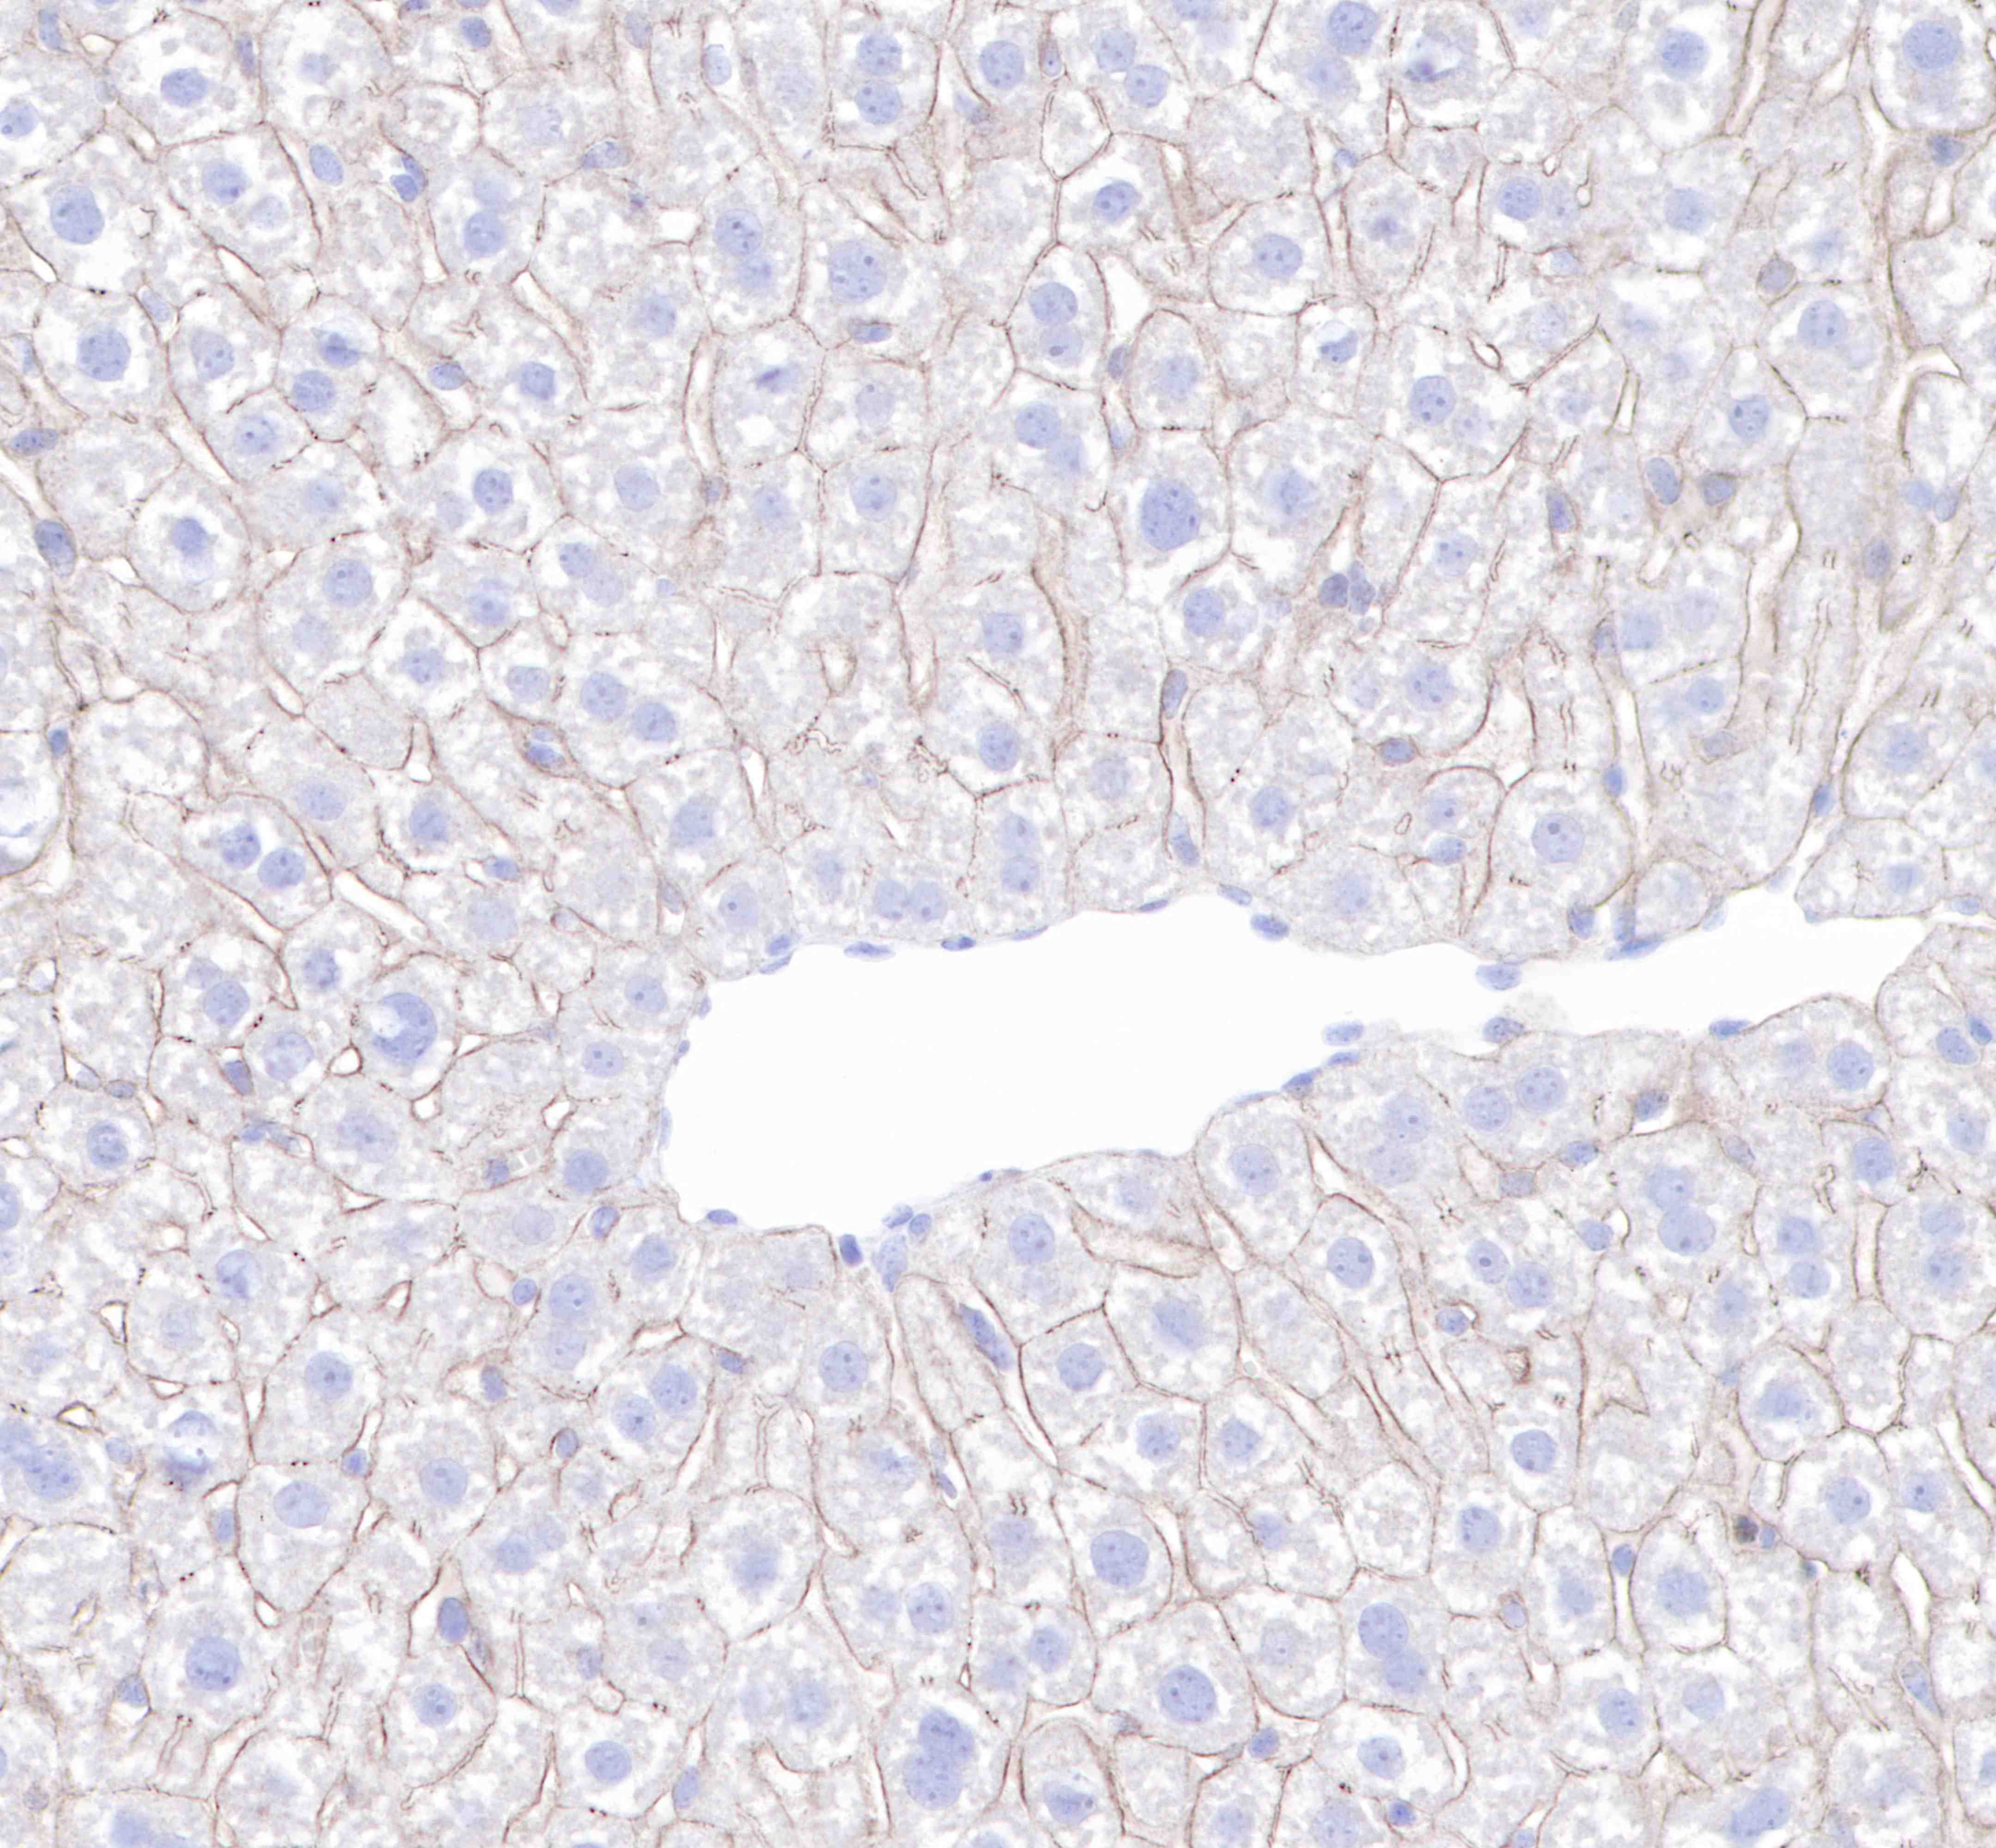

| IHC-P |

1:250 |